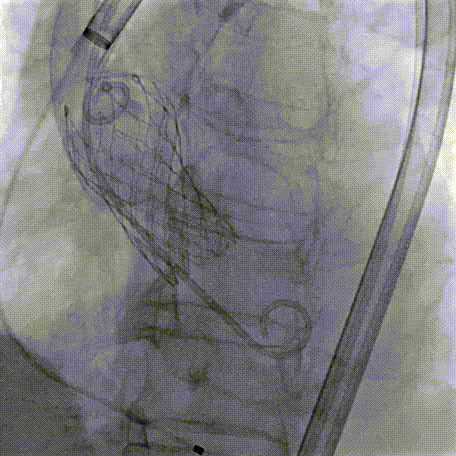

Step 1.升主动脉情况评估

Step 2.建立大鞘通路:大鞘通过升主、边进入边加弯,避免剐蹭弓部斑块

Step 4.输送系统进入:过弓性能优异,悬空通过,整体过程未将鞘管顶起至弓顶部

Step 5.瓣膜定位与释放:高起始位逐渐向下推送保持良好同轴性,无位移

Step 6.工作位观察:真实瓣环下方2mm,位置合适,决定释放,一次完成

Step 7.瓣膜脱钩:脱钩稳定无位移

Step 8.最终造影:真实瓣环下方3mm标准位,完全同轴,轻微反流,猪尾撤出后反流完全消失

过弓示意图